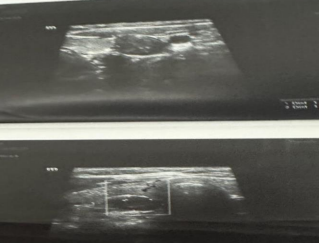

A requested abdominal CT scan showed stage E pancreatitis of balthazar with peripancreatic ; perisplenic FLUID infiltration and at the level of the parietocolic gutters without stones or dilation visible in the intrahepatic and main bile ducts (Figure 1) with on cervical ultrasound two inferior retrothyroid nodular formations measuring on the right 15.5/15.2mm and left22/16.8/13mm ovals with irregular contours in places, strongly hypoechoic, site of microcalcifications and vascularized in doopler (figure2); The rest of the thyroid parenchyma was normal in appearance and volume.

Figure 1: abdominal CT scan showed stage E pancreatitis of Balthazar

Figure 2: cervical ultrasound two inferior retrothyroid nodular formations measuring on the right 15.5/15.2mm and left22/16.8/13mm ovals with irregular contours in places, strongly hypoechoic, site of microcalcifications and vascularized in doopler(figure2); The rest of the thyroid parenchyma was normal in appearance and volume.